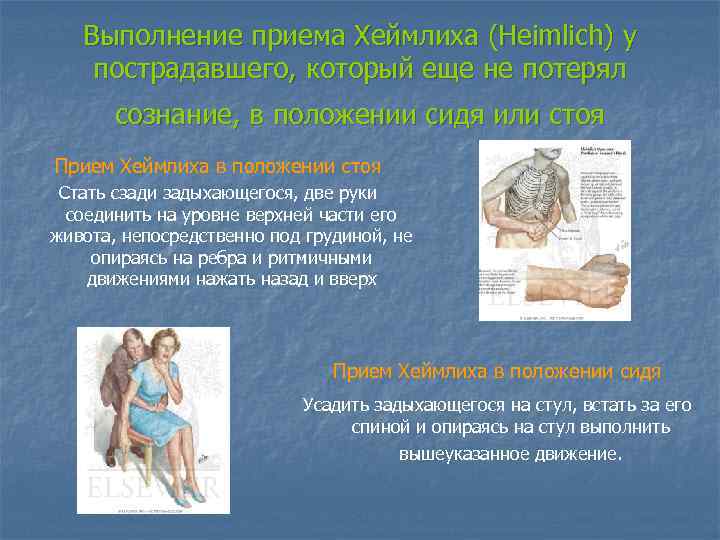

Выполнение приема Хеймлиха (Heimlich) у пострадавшего, который еще не потерял сознание, в положении сидя или стоя Прием Хеймлиха в положении стоя Стать сзади задыхающегося, две руки соединить на уровне верхней части его живота, непосредственно под грудиной, не опираясь на ребра и ритмичными движениями нажать назад и вверх Прием Хеймлиха в положении сидя Усадить задыхающегося на стул, встать за его спиной и опираясь на стул выполнить вышеуказанное движение.